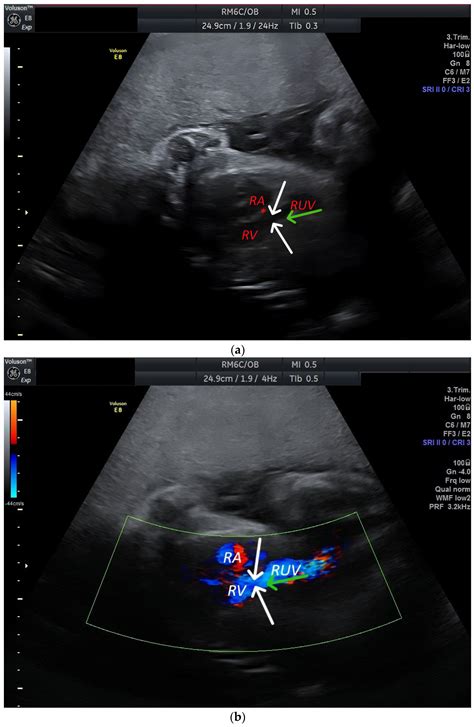

The identification of a Persistent Right Umbilical Vein is primarily achieved through high-resolution fetal ultrasonography. During the mid-trimester scan (typically between 18 and 22 weeks), sonographers examine the fetal abdomen to ensure that the umbilical vein is entering the liver correctly. When a PRUV is present, the sonographer will observe the following characteristic signs:

• The umbilical vein courses to the right side of the gallbladder, rather than the left.

• The vessel takes a slightly different anatomical path toward the portal system.

• The color Doppler ultrasound shows a change in the direction of the vascular flow compared to the expected norm.

Because these findings can be subtle, ultrasound technicians and maternal-fetal medicine specialists are trained to look for these specific markers when the abdominal anatomy does not appear completely symmetrical. Once identified, the radiologist or obstetrician will conduct a detailed survey of the entire fetus to rule out any associated structural abnormalities.